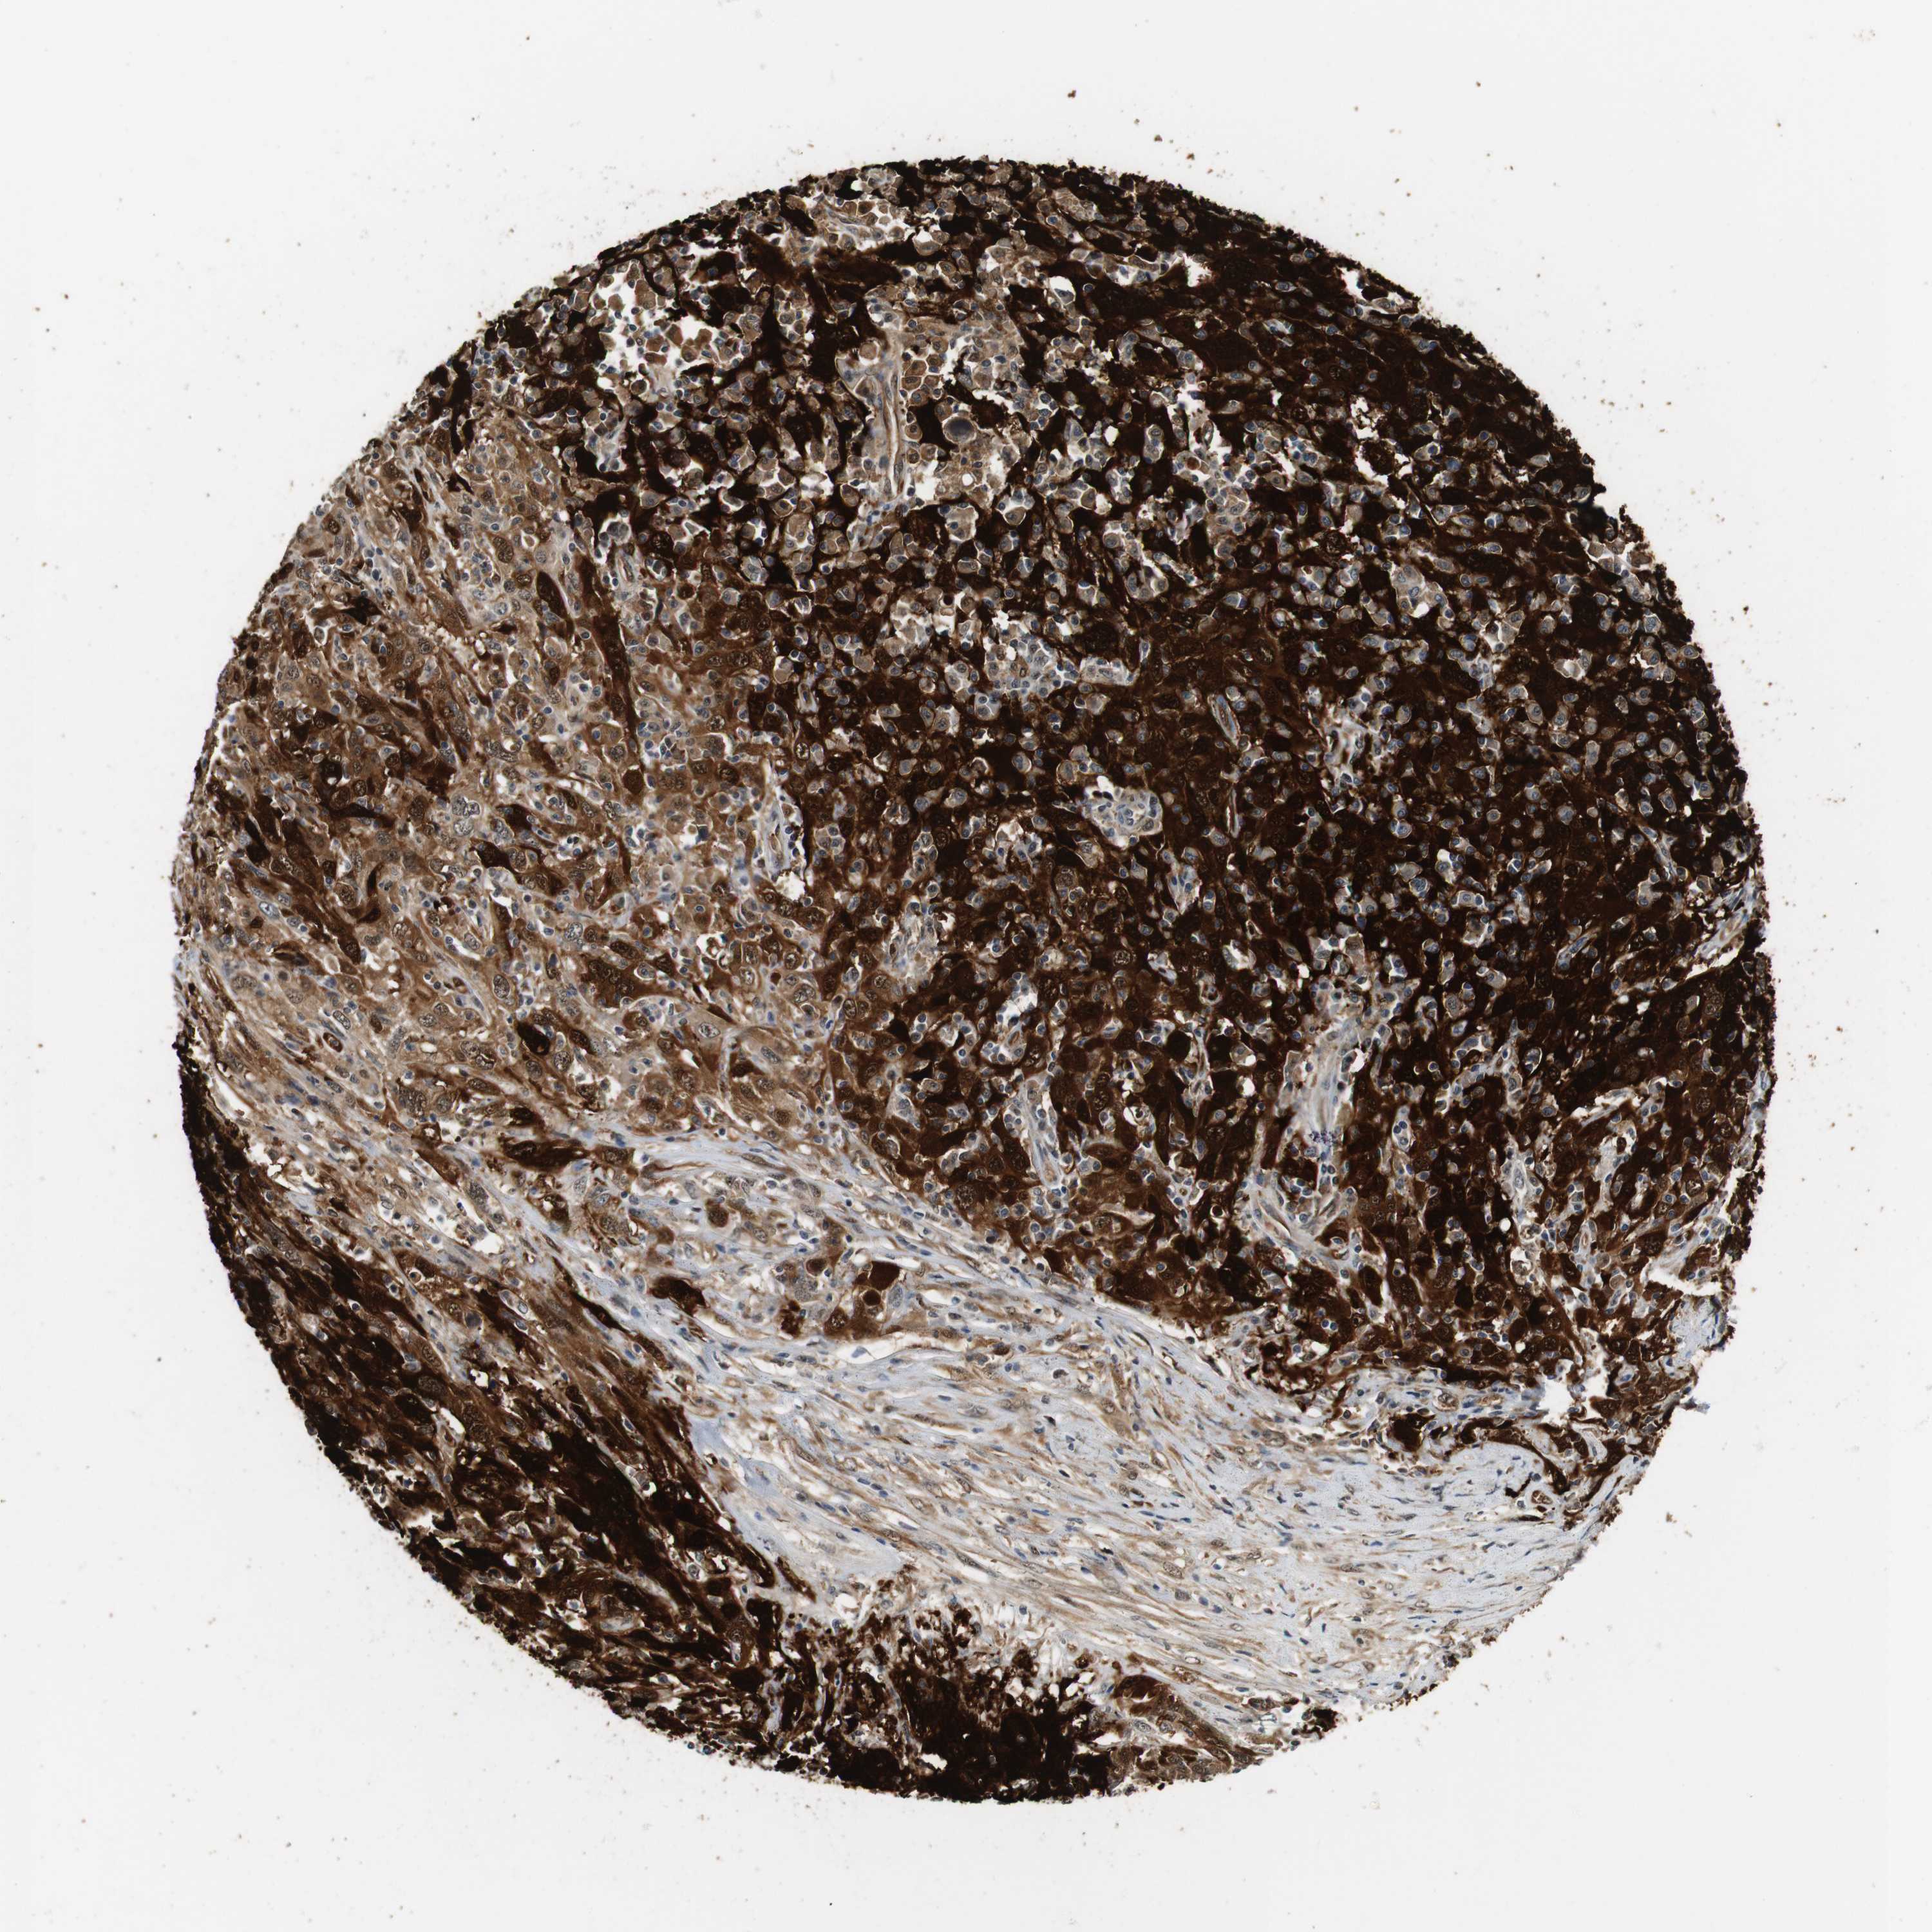

CERVICAL CANCER - Protein expressioni

A mouse-over function shows sample information and annotation data. Click on an image to view it in a full screen mode. Samples can be filtered based on level of antibody staining by selecting one or several of the following categories: high, medium, low and not detected. The assay and annotation is described here.

Note that samples used for immunohistochemistry by the Human Protein Atlas do not correspond to samples in the TCGA dataset.

Antibody stainingi

Antibody staining in the annotated cell types in the current human tissue is reported as not detected, low, medium, or high, based on conventional immunohistochemistry profiling in selected tissues. This score is based on the combination of the staining intensity and fraction of stained cells.

Each image is clickable and will lead to virtual microscopy that enables deeper exploration of all samples and also displays staining intensity scores, fraction scores and subcellular localization as well as patient and tissue information for each sample.

Antibody HPA014179

Antibody CAB025128

Staining

High

Medium

Low

Not detected

Intensity

Strong

Moderate

Weak

Negative

Quantity

>75%

75%-25%

<25%

None

Location

Nuclear

Cytoplasmic/membranous

Cytoplasmic/membranous,nuclear

Squamous cell carcinoma, NOS

Adenocarcinoma, NOS